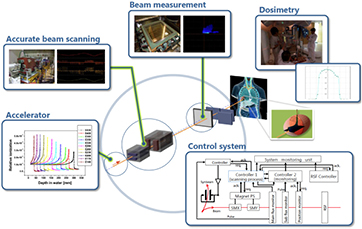

Standard image High-resolution imageGenerally speaking, these processes (described in section 3) are fairly well understood, even if often not with the accuracy desirable for cancer therapy. The particle range, which is essential for irradiating the tumor, and not the surrounding organs at risk (OAR) in the Bragg peak region, can be calculated by the stopping power. As shown in figure 2(B), the narrow pristine Bragg peak must be extended to cover all the tumor area (spread-out-Bragg-peak, SOBP). This can be done either by passive modulation of the primary beam, or by changing the energy while raster scanning tumor slices with a pencil beam (figure 5). Scanning provides superior dose distributions compared to passive modulation, and greatly reduces the production of secondary neutrons, which may represent a risk for secondary cancers (see section 4.4). However, the interplay between pencil beam scanning and organ movement (figure 6) caused by breathing jeopardizes the dose distribution, and makes treatment of moving targets—e.g. lung tumors—with spot scanning much more complicated than with passive modulation (Bert and Durante 2011). The range uncertainty, due to organ movements and other causes (see section 5), requires to deliberately deliver a higher range as prescribed in order to avoid missing part of the tumor. This in turn can move the SOBP into an OAR, thus increasing toxicity. Lateral scattering broadens the beam and creates an undesired penumbra. Figure 7 shows that the penumbra is reduced by increasing the atomic mass of the ion used in therapy (see section 3.2). Nuclear interactions generate slow target fragments, which give a small contribution to the dose but can have high biological effectiveness. If particles heavier than protons are used, projectile fragmentation produces fast fragments with a mean velocity similar to the velocity of the primary ion. These fragments have lower mass and therefore higher range than the primary ions (see section 3.1), thus generating a longitudinal tail in the Bragg curve (figure 2). The angular distribution of the fragments is narrow in the forward direction, but the spread of the lighter fragments (protons and helium) contributes to the lateral widening of the beam.

2.5.2. Beam delivery: fast and accurate.

More than 90% of the proton therapy patients have been treated so far with passive beam modulation (figure 5). However, now virtually all the new machines have pencil beam scanning, which offers much more robust field characteristics. Scanning offers a superior dose distribution, and a reduced dose to distal organs, which is a concern for second cancers. This means that the clinical results so far reported have been obtained with a sub-optimal method, and much better results are expected with scanning. But beam scanning delivery is still too slow at most centers which can be problematic for moving tumors. Speed and motion mitigation strategies are a priority for treating common tumors such as those in the thorax and abdomen. Innovative solutions such as patient-specific ridge filters and tracking are under study to tackle these problems. Gantries are also generally deemed as necessary in CPT. While all protontherapy facilities offer rotating gantries, the magnet size grows by increasing the charge, and therefore the rigidity, of the ions. At the moment only HIT is equipped with a rotating gantry for C-ions, a 670 tons, 13 m diameter gigantic steel construction that can be rotated with sub-mm precision. All other C-ions centers used fixed beam ports (0°, 90° and in some cases 45°). New solutions using superconductive magnets are urgently needed.

2.5.3. Treatment planning: physics and biology.

Treatment of a patient with pencil beam scanning is uniquely tailored for that patient and requires many different parameters. Each of these parameters has uncertainties. The error on the particle stopping power in a given tissue can shift 3–5% the prescribed range. Monte Carlo codes can be the ideal tools for precise plan calculations, but they must be faster to find daily clinical applications, and need accurate reaction cross-sections in useful target materials for the energy range of interest. Measurements of double-differential fragmentation cross sections are essential for heavy ion therapy, while target fragmentation is important also in protontherapy. These are 'classical' nuclear physics measurements, even if they are time-consuming and complex, and may represent a major contribution of 'old' nuclear physics to 'new' cancer therapy. In addition, new centers will try to exploit different ions beyond 1H and 12C, and treatment plans should add the ion atomic number Z to the optimization. However, the physical dose in Gy for charged particles does not reflect the biological effects in the tumor and the normal tissue. The plan optimization must also include the biological effectiveness of the beam, taking into account the intra-tumoral heterogeneity (hypoxia, cancer stem cell niches, etc). Development of robust radiobiological models is essential to exploit the full benefit of particle therapy, and require a careful physical characterization of the beam interaction down to the nm size. Beyond the RBE, major breakthrough can be expected by particle radiobiology, e.g. in the emerging field of radioimmunotherapy, and new biophysical models will be necessary to incorporate these new data.